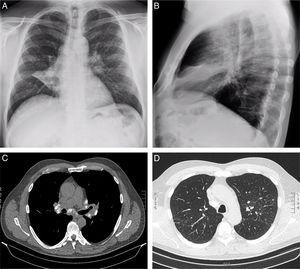

(A) Posteroanterior and (B) lateral chest radiographs showing bilateral reticulonodular opacities, hilar lymphadenopathy, and increased density with middle lobe atelectasis. (C) Chest CT scan in mediastinal window showing calcified mediastinal and hilar lymph nodes bilaterally. (D) Chest CT scan in lung window showing a bilateral micronodular interstitial pattern.

We report the case of a 60-year-old man, a wire-drawing worker with 29 years of occupational exposure to calcium stearate, who presented to the Pulmonology Department with pleuritic pain in the right hemithorax. Spirometry values were within normal limits. Chest radiography revealed bilateral reticulonodular opacities, hilar lymphadenopathy, and increased density with atelectasis of the middle lobe. CT scan showed a partially calcified progressive massive fibrosis mass in the right upper lobe with major fissure retraction, a bilateral micronodular interstitial pattern, and calcified mediastinal and hilar lymphadenopathy (Fig. 1). Bronchoscopy demonstrated partial stenosis of the middle lobe bronchus due to extrinsic compression. Bronchoalveolar lavage (BAL) was performed in the lingula, and five transbronchial cryobiopsies were obtained from the left upper lobe. BAL cytology showed: neutrophils 51%, lymphocytes 32%, eosinophils 8%, macrophages 4%, with a CD4/CD8 ratio of 2.04. Histological examination (Masson's stain) revealed peribronchiolar fibrosis, granulomas with multinucleated giant cells (CD68 positive), and an inflammatory infiltrate (CD45 positive), with no evidence of malignancy. Mineralogical analysis by infrared spectroscopy identified calcium stearate in lung tissue, establishing the diagnosis of pneumoconiosis due to calcium stearate. The patient was referred to the Occupational Pulmonology Unit for follow-up.